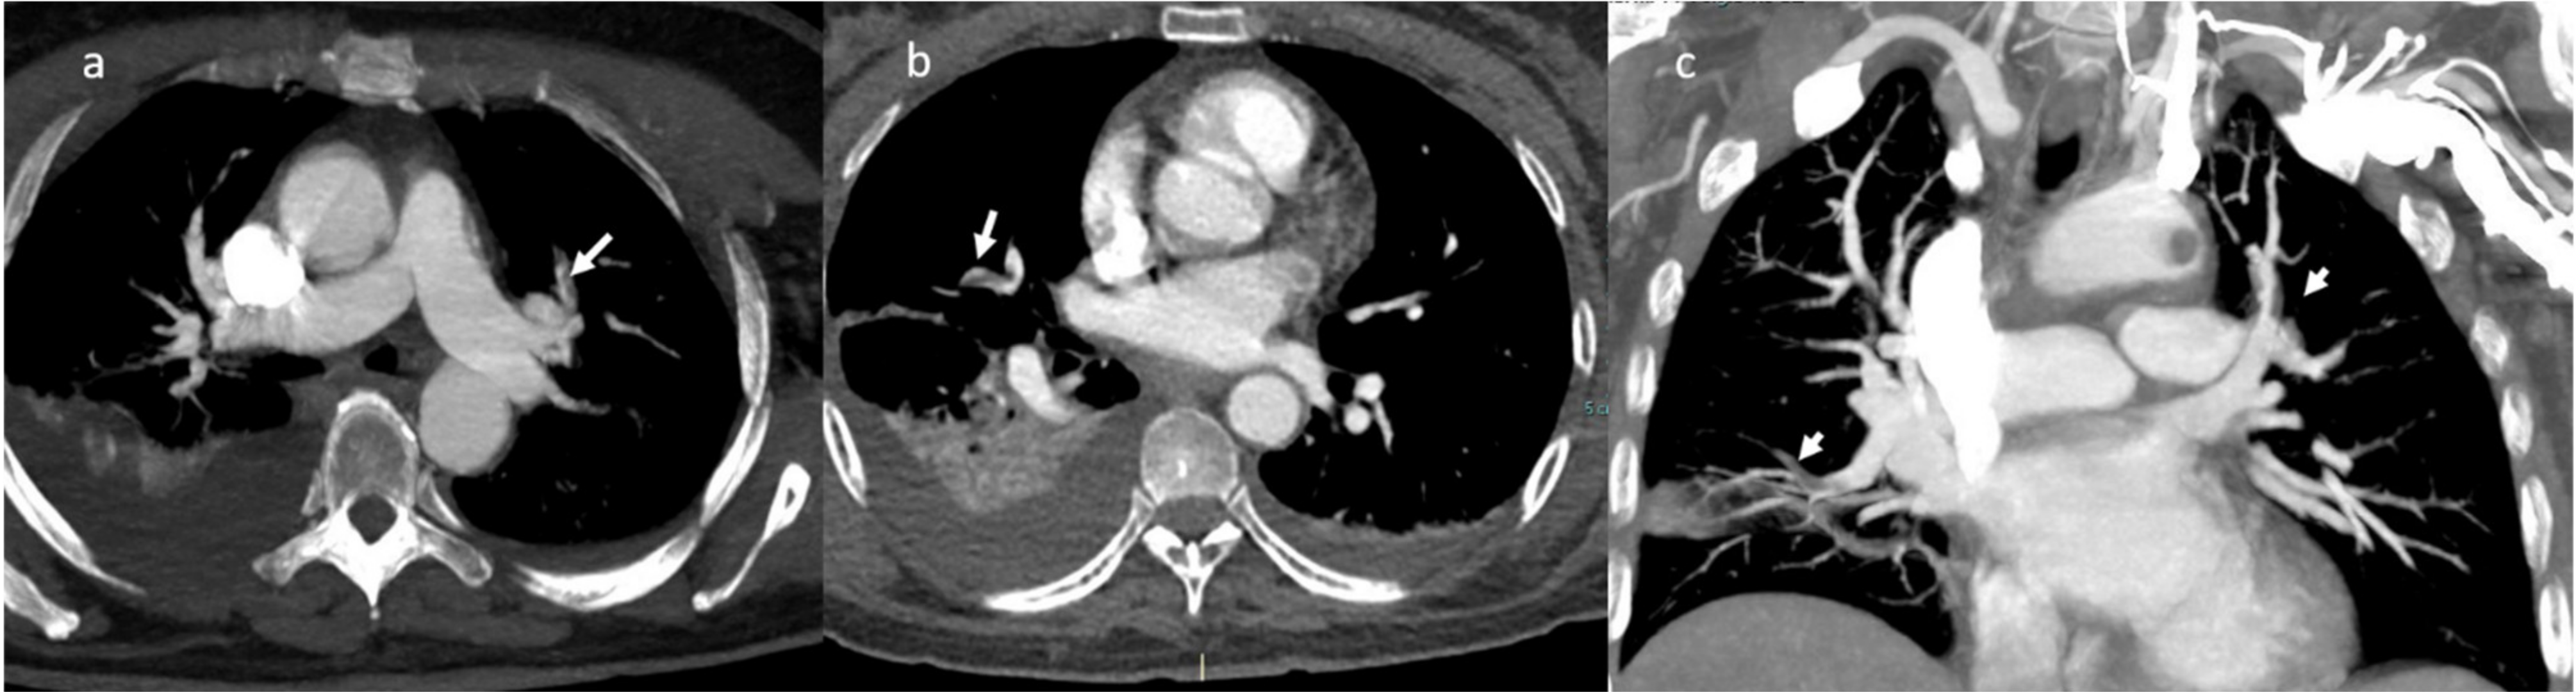

A successive thorax angio-CT added the findings of multiple contrast filling defect with multi-vessel involvement: at the level of the left upper lobe segmental branches, of left interlobar artery, of the right middle lobe segmental branches and of the right interlobar artery (Figure 4).

Figure 4.

CT-angiography: presence of multiple contrast filling defects involving the left upper lobe segmental branches (a), the right segmental artery (b); MPR coronal plane in (c).